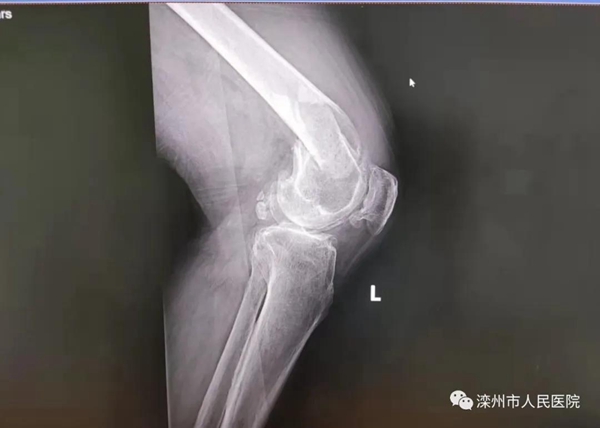

老大爺年近八旬,灤州市榛子鎮(zhèn)人,平素有“左膝關(guān)節(jié)骨性關(guān)節(jié)炎”病史7年,行走不便,在家中摔傷致左股骨髁上粉碎骨折。急診入院查體:左大腿下段腫脹畸形明顯,劇痛,左膝關(guān)節(jié)主被動活動受限。醫(yī)師予左脛骨結(jié)節(jié)牽引、止痛、預(yù)防血栓藥物治療,全面完善各項(xiàng)術(shù)前檢查。加強(qiáng)指導(dǎo)患者進(jìn)行雙下肢踝泵運(yùn)動及股四頭肌收縮功能練習(xí),堅(jiān)持呼吸功能訓(xùn)練及體位訓(xùn)練。檢查結(jié)果示:左股骨髁上骨折,斷端移位;左膝關(guān)節(jié)退變、關(guān)節(jié)間隙變窄;重度骨質(zhì)疏松;頸動脈硬化伴斑塊;左心室舒張功能減低;雙肺炎性病變、胸腔少量積液。